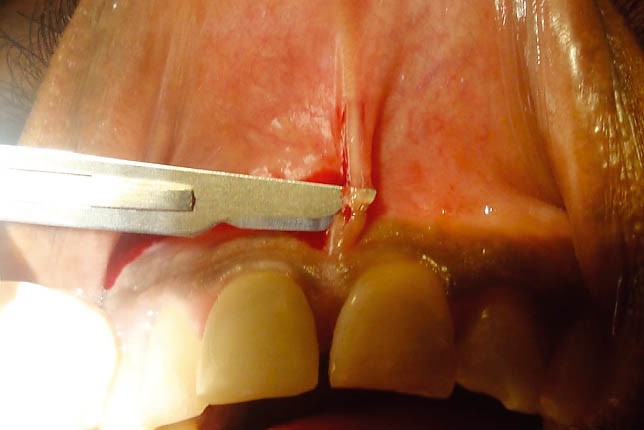

Sadalanan məhdudiyyətlərin ortadan qaldırılması və ya önünə keçilməsi məqsədilə frenulumun tamamən uzaqlaşdırılması (frenektomiya) həyata keçirilir. Bu prosedur həm ənənəvi cərrahi həm də lazer cərrahiyyəsi metodu ilə aparılır. Hansı metodun tətbiq edilməsi hər bir kliniki halda fərdi şəkildə qərara alınır.